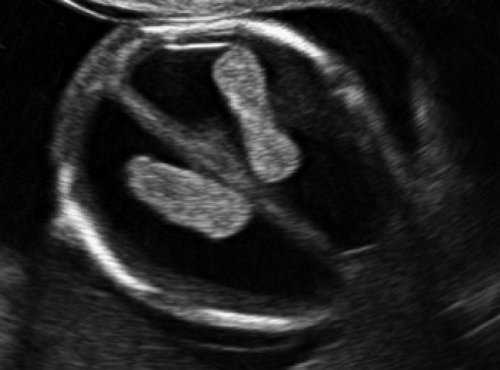

Самый тяжелый и инвалидизирующий порок в области задней черепной ямки - аномалия Денди-Уокера, характеризующаяся наличием кистозного образования в области большой цистерны с аплазией червя мозжечка. Наш опыт показывает, что в I триместре в срок 12 недель при осмотре аксиального среза головы плода можно визуализировать кистозное образование в области задней черепной ямки, однако провести дифференциальный диагноз между различными патологиями этой области, имеющими разный прогноз, по этому скану невозможно (рис. 9).

Рис. 9. Аксиальный срез головы плода, киста задней черепной ямки, беременность 12 недель.

В то же время в среднесагиттальном скане была найдена расширенная большая цистерна, которая "сливалась" с IV желудочком, из-за отсутствия червя мозжечка. При осмотре "осьминожки" отсутствовала полноценная нижняя ножка, ввиду слияния ее с кистой в области большой цистерны (рис. 10).

Рис. 10. Аномалия Денди-Уокера, беременность 12 недель. Среднесагиттальный скан. Киста в области большой цистерны, сливающаяся с IV желудочком.

Визуализируется сосудистое сплетение IV желудочка на границе слияния.

Красный цвет - деформированная "осьминожка"; желтый цвет - киста в области большой цистерны; синий цвет - воротниковое пространство.